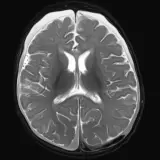

Over 2,100 interactive radiology cases, curated by radiologists for your level of training. Scroll, window, and view cases full screen — just like on PACS. Click linked findings in each writeup to jump straight to them on the image. Cases include sample reports, a focused discussion section, original illustrations, and videos.

Neuro Fellowship — a course tailored for fellows and practicing radiologists with in-depth reviews of advanced neuro topics like brain tumors, featuring rare diagnoses, differentials, and clinical pearls.

Des cas entièrement interactifs avec les outils attendus d'un PACS — défilement, fenêtrage, zoom, déplacement, mesures, ROI et mode plein écran.

Des annotations détaillées mettent en évidence les résultats clés directement sur les cas. Cliquez sur les résultats liés dans les descriptions de cas pour accéder à leur emplacement exact sur l'examen.